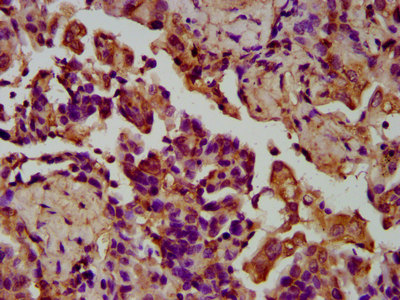

IHC image of PACO58288 diluted at 1:200 and staining in paraffin-embedded human lung cancer performed on a Leica BondTM system. After dewaxing and hydration, antigen retrieval was mediated by high pressure in a citrate buffer (pH 6.0). Section was blocked with 10% normal goat serum 30min at RT. Then primary antibody (1% BSA) was incubated at 4°C overnight. The primary is detected by a biotinylated secondary antibody and visualized using an HRP conjugated SP system.